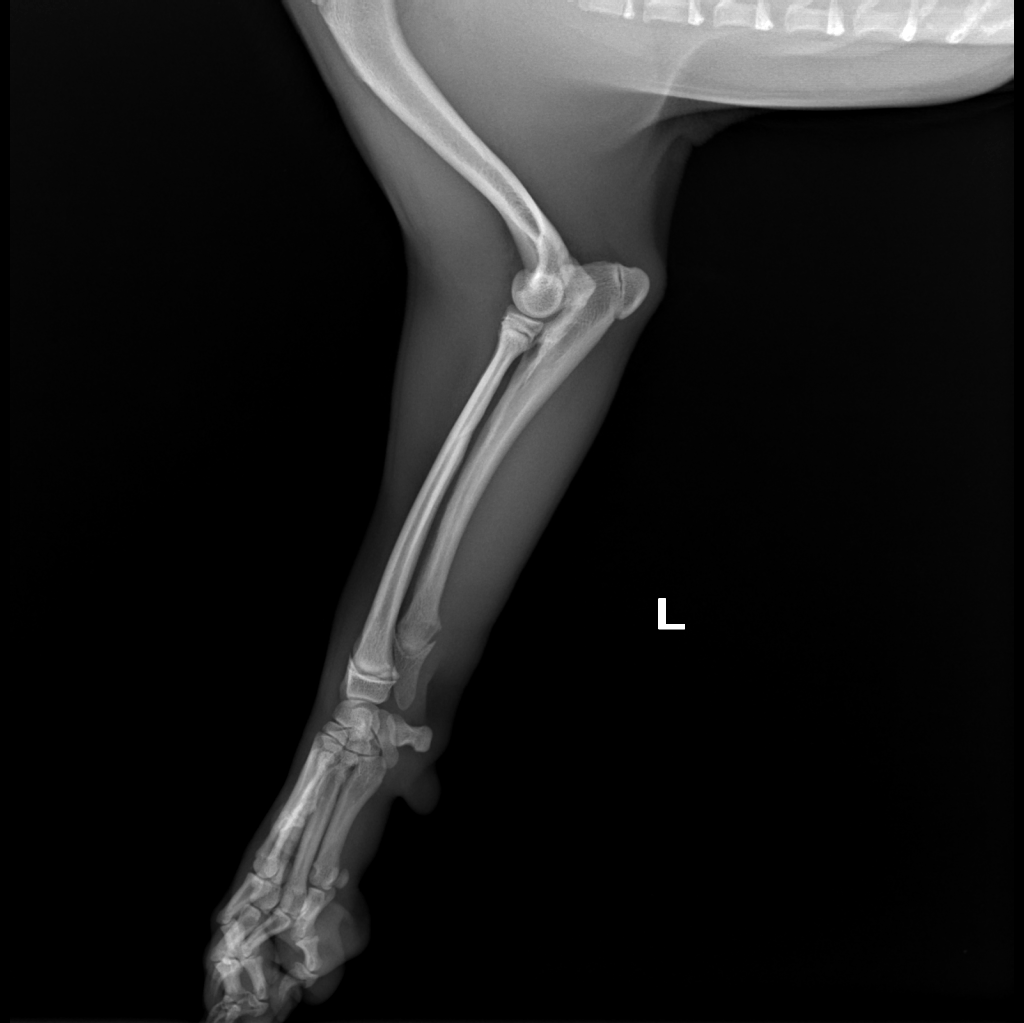

Male, 7 months old, 5 kg Pug dog

The reason of orthopedic consultation was left carpus valgus

Orthopedic examination reveals bilateral carpus valgus, more evident on the left forelimb,

bilateral abduction of antebrachium, no evident lameness.

Radiographic exam and CT scan of forelimbs was performed

Diagnostic imaging reveal bone density alterations affecting the distal ulnar physis, bilaterally, characterized by bone rarefaction, retention of the cartilaginous core and irregular ossification.